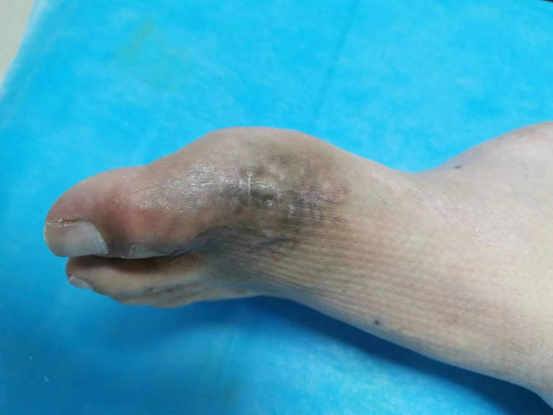

病例二:左足痛风石形成破溃感染

痛风病史8年,左足痛风石形成破溃感染,行痛风石清除扩创,抗生素骨水泥占位。